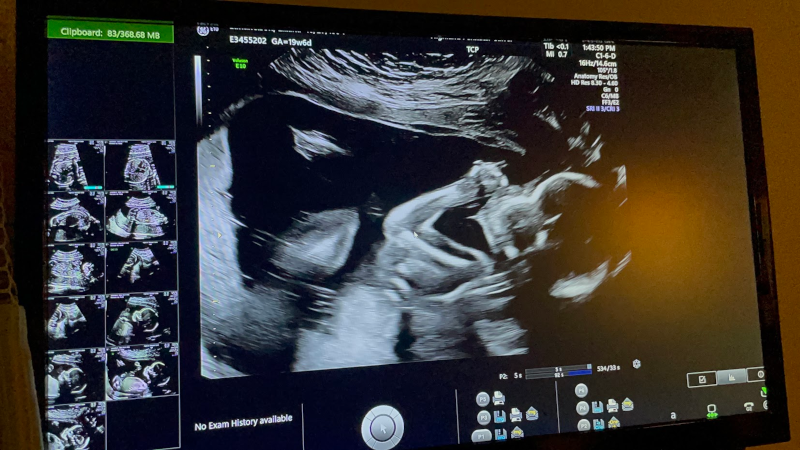

We walked into the ultrasound room, filled with a mixture of excitement and apprhension, hoping that our child would be viable. Lili lay down, and the technician got to work. “The jelly is warm!” Lili commented, pleasantly surprised that it wasn’t freezing cold. The first image of our child was projected on the screen before us, and we couldn’t stop smiling. One by one the technician catalogued the baby’s parts, their humeri, femurs, the valves of the heart, the fingers, the toes, the brain, the spine, and more–we got to see it all. Our hope bloomed and meshed with reality. The baby was fine. And wiggled a lot. It was positively magical to watch.